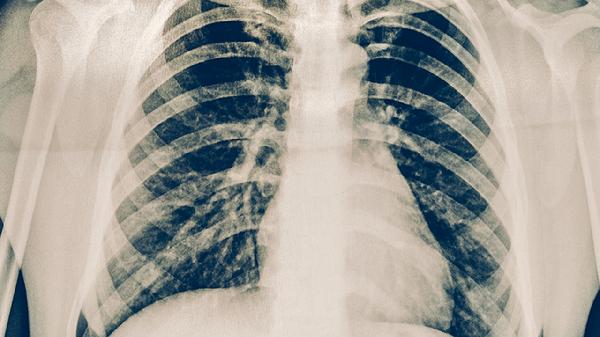

空洞型肺结核能治好吗?严重吗?

大多数情况下,空洞型肺结核本身不会直接危及生命,但如果治疗不规范,可能会引发严重的后果。疾病的进展与是否按时接受治疗、身...